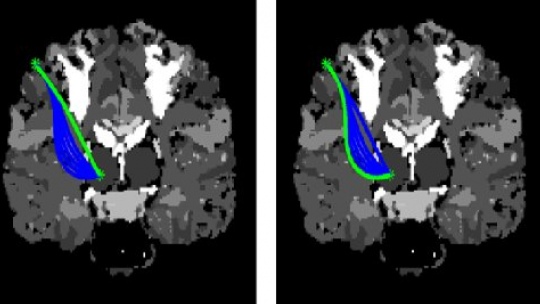

Risk Minimization

The brain is very important and delicate organ, some areas serve key functionality, where trauma will be fatal (the white area). Surgery paths avoid such areas. The planning software first generates many safe paths, likes growing a tree.

Smooth&Bounded Curvature

The path is refined further because of the bending (curvature) behaviour of the flexible STING, which only bends gradually with a limit.